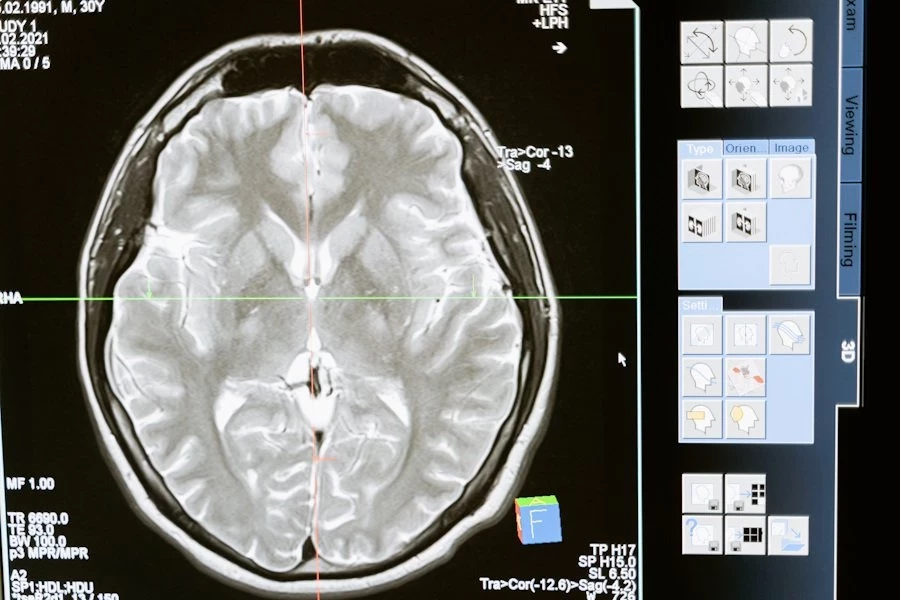

NEJM: комбинация препаратов уменьшила опухоли головного мозга на 91%

В Harvard Medical School ученые разработали новое лечение для редких опухолей головного мозга, называемых папиллярными краниофарингиомами. Их методика выдала потрясающие результаты в уменьшении размеров опухоли. Они опубликовали свою методику в журнале New England Journal of Medicine.

В исследовании приняли участие 16 пациентов, из которых 15 прошли как минимум один полный цикл терапии с использованием комбинации препаратов в течение 28 дней. После четырех таких циклов средний размер опухоли сократился на 68% до 99%, в среднем на 91%.